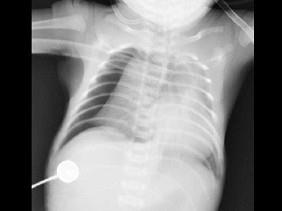

问题 男,12天。呼吸困难,哭闹不止。X线检查如图,最可能的诊断为?(?)

选项 A.新生儿胸腔积液 B.新生儿心包积液 C.新生儿白肺 D.新生儿肺炎 E.新生儿气胸

答案 E